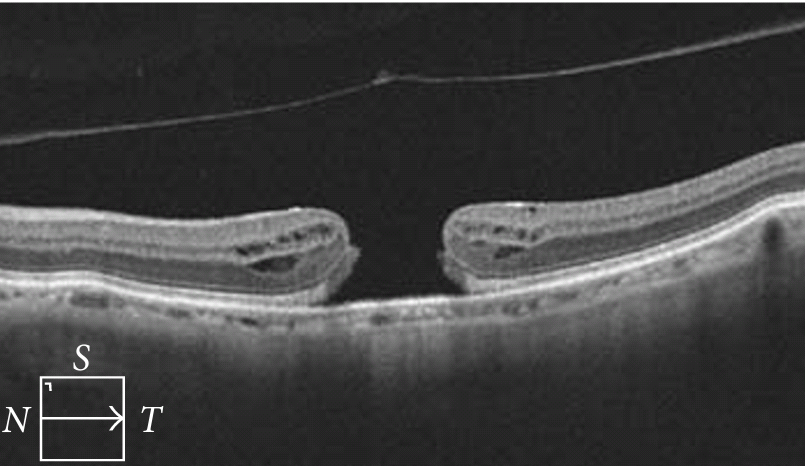

Рисунок » Макулярное отверстие»